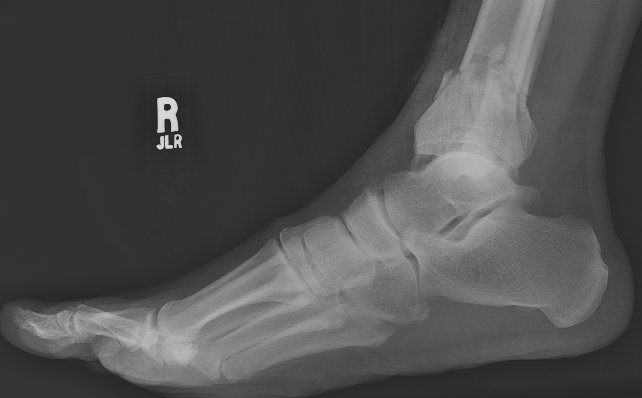

Return to Tibia and Fibula Fractures